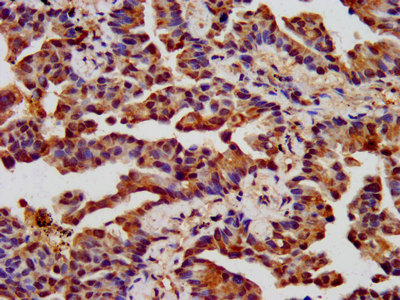

IHC image of CSB-PA005397LA01HU diluted at 1:400 and staining in paraffin-embedded human endometrial cancer performed on a Leica BondTM system. After dewaxing and hydration, antigen retrieval was mediated by high pressure in a citrate buffer (pH 6.0). Section was blocked with 10% normal goat serum 30min at RT. Then primary antibody (1% BSA) was incubated at 4°C overnight. The primary is detected by a biotinylated secondary antibody and visualized using an HRP conjugated SP system.